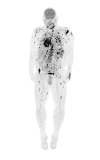

Figure 2. Scanning PET/CT scan.

PET/CT showing innumerable hypermetabolic lesions in the cutaneous surfaces with multiple hypermetabolic osseous and intramuscular lesions throughout the axial and appendicular regions. Additionally, there are hypermetabolic lesions in the brain, thoracic and lumbar spine, pulmonary tissue, salivary glands, heart, bowels, liver, spleen, bilateral adrenal glands, pancreas, and peritoneum and throughout the abdominal wall.